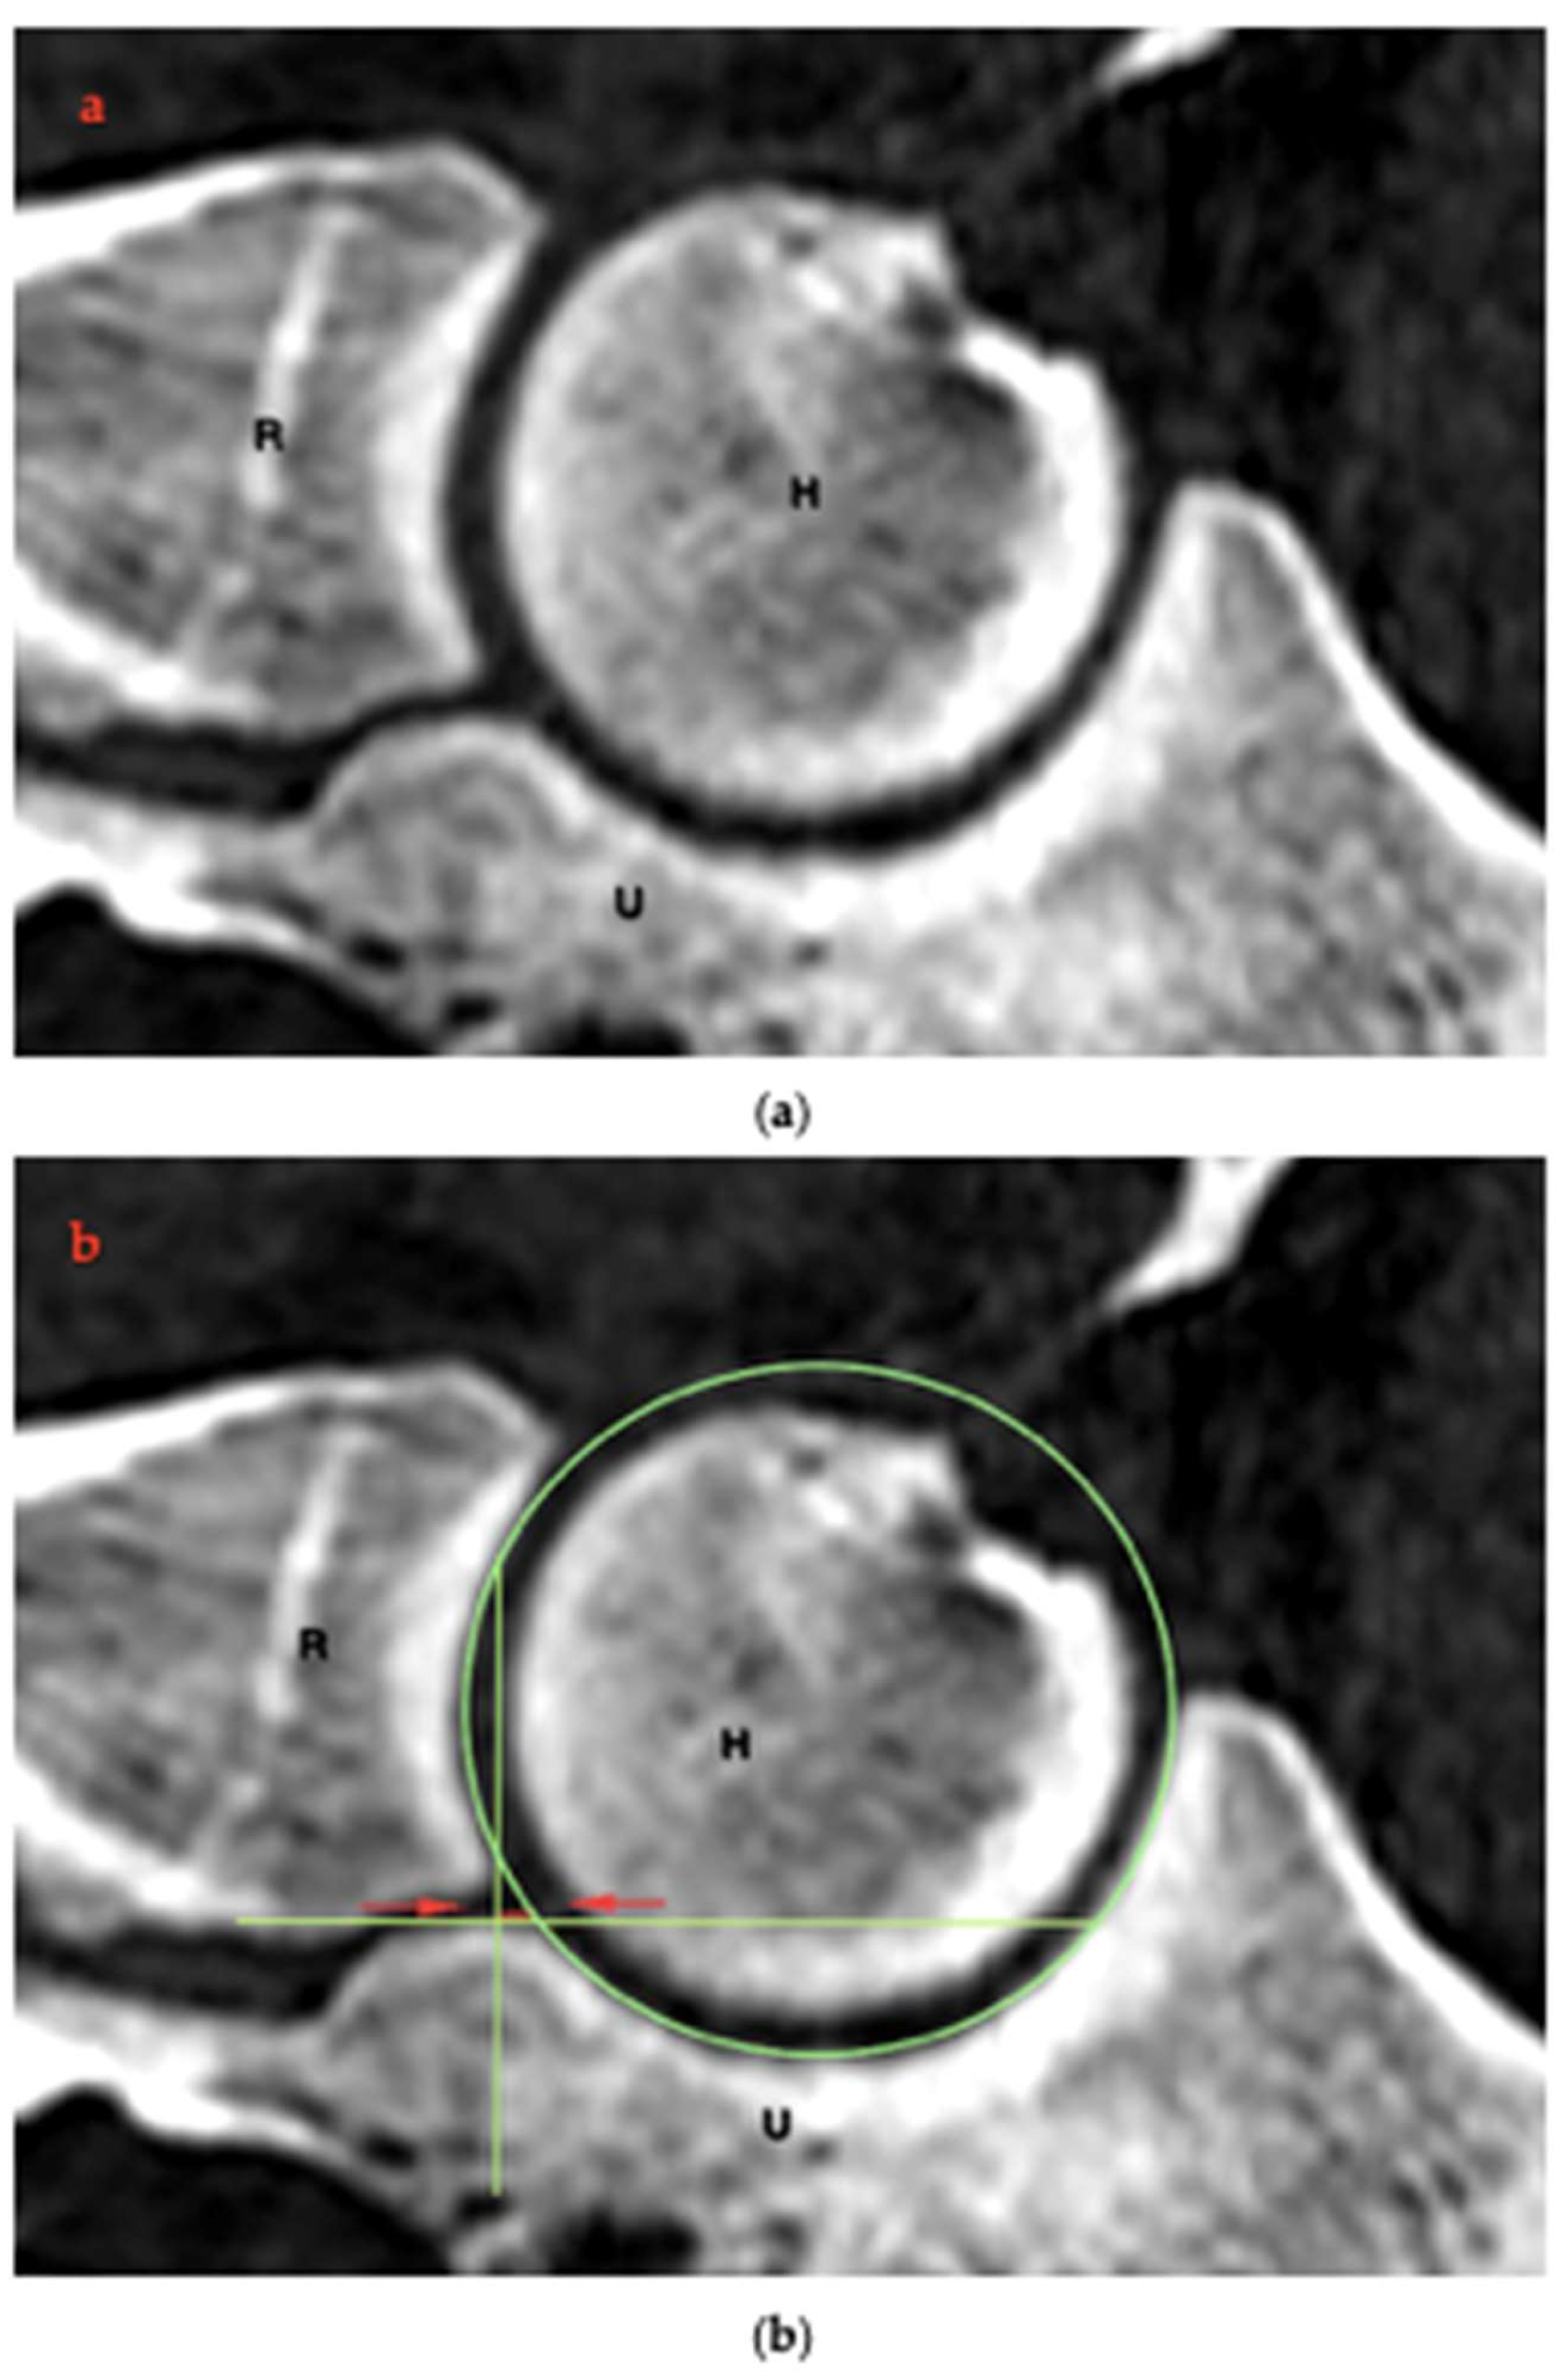

2.4. RUI Measurements